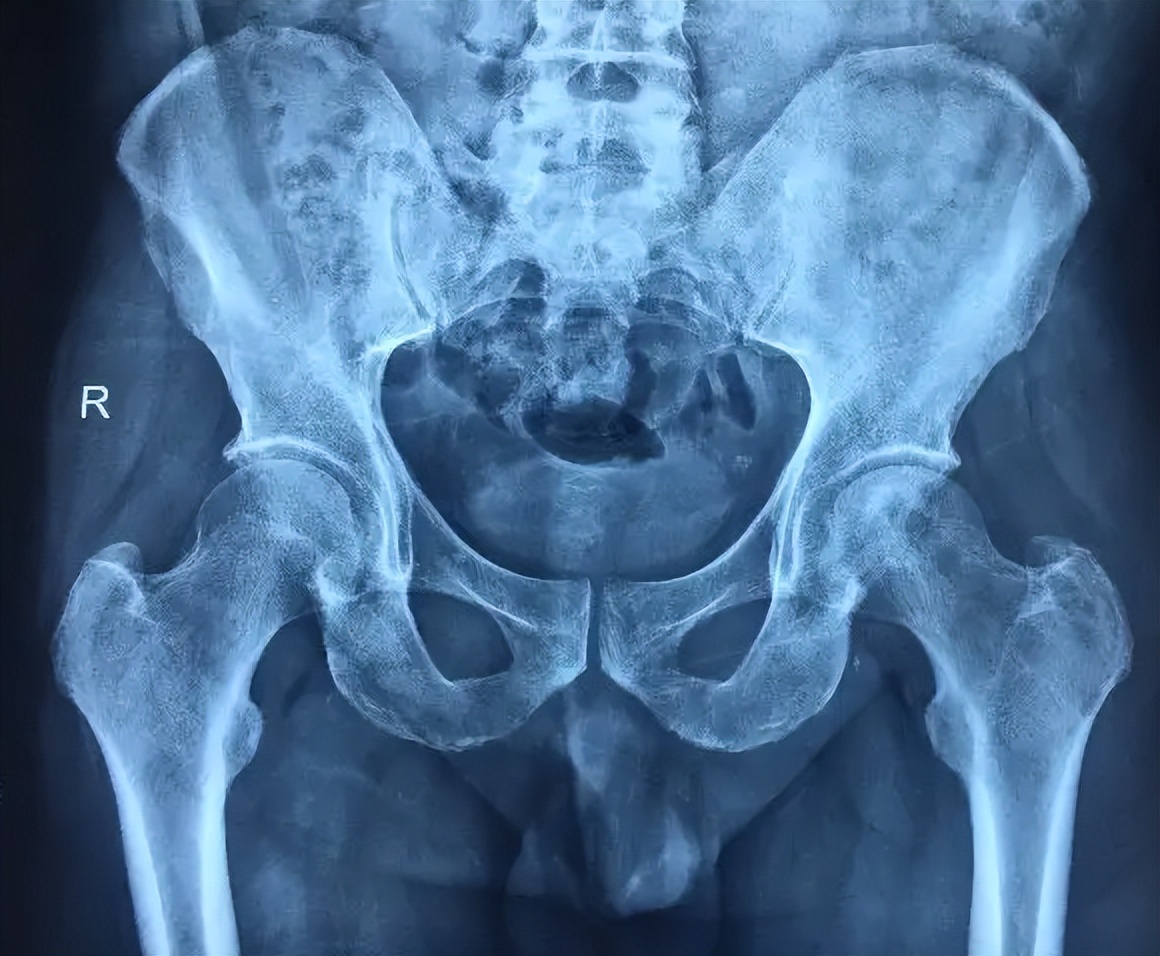

股骨头治疗的方法主要有两种,一种是保守治疗,另一种手术治疗。保守治疗主要包括避免患肢负重,包括部分负重或者完全不负重。对于比较严重的股骨头坏死,可采用手术治疗。手术治疗包括髓心减压、截骨手术、髓芯减压加植骨手术、带血管蒂的骨植入手术,还有多孔钽金属植入手术。

1、保守治疗:Ⅰ-Ⅲ期患者可坐轮椅或扶拐行走,以减少股骨头负荷,避免股骨头出现塌陷;也可使用促进骨生成药、降脂药和活血化瘀、通络祛湿的中药;

2、手术治疗:对于Ⅰ-Ⅲ期患者可行髓芯减压术、带血管腓骨移植术、带血管髂骨移植术等;对于严重股骨头坏死患者应进行髋关节融合术、经股骨粗隆部旋转截骨术或人工关节置换术。